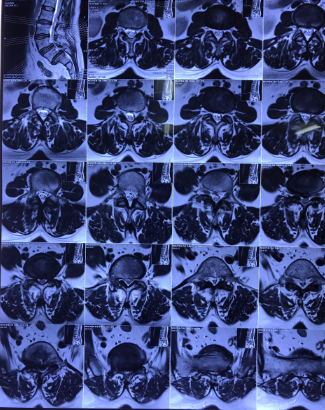

Sau khi hội chẩn, bệnh nhân được chỉ đỉnh phẫu thuật cố định cột sống và hàn xương liên thân đốt lối sau qua lỗ liên hợp (TLIF). 4 ngày sau phẫu thuật, bệnh nhân đã có thể ngồi dậy, tập đi lại trong khung tập đi, triệu chứng lâm sàng đã giảm đi rõ rệt: không còn cảm giác đau lan dọc 2 chân, cảm giác 2 chân trở nên nhẹ nhàng hơn, chỉ còn đau nhẹ vết mổ.

Hình ảnh: X Quang bệnh nhân sau phẫu thuật hàn xương, nắn chỉnh cột sống